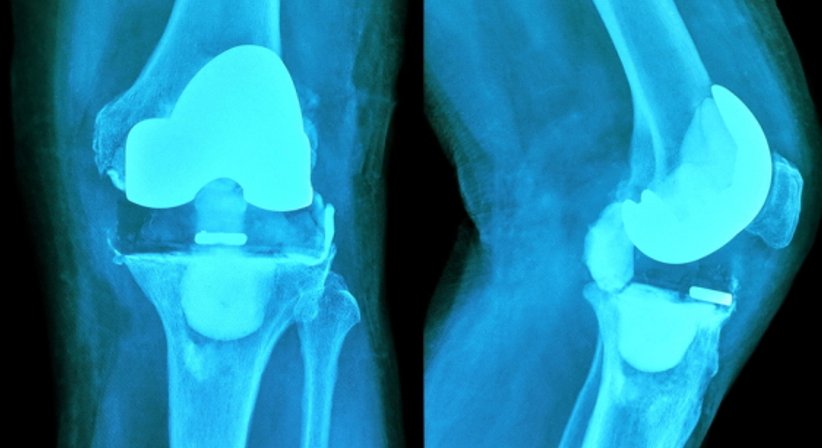

Bei einer Knietotalendoprothese (Knie-TEP) wird das verschlissene bzw. zerstörte Kniegelenk zur Gänze durch ein künstliches Gelenk ersetzt.

Das künstliche Kniegelenk (Prothese), das ähnlich komplex wie das natürliche Kniegelenk aufgebaut ist, wird im Rahmen eines chirurgischen Eingriffs fest im Knochen verankert.